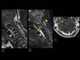

Hangman fracture

Hangman's fracture is the colloquial name given to a fracture of both pedicles, or pars interarticulares, of the axis vertebra (C2). Causes The injury mainly occurs from falls, usually in elderly adults, and motor accidents mainly due to impacts of high force causing extension of the neck and great axial load onto the C2 vertebra. [Source: Wikipedia ]